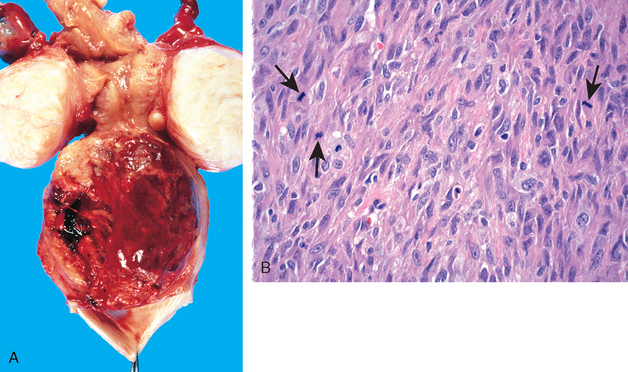

Morphology. Leiomyosarcomas grow within the uterus in two somewhat distinctive patterns: bulky, fleshy masses that invade the uterine wall, or polypoid masses that project into the uterine lumen (Fig. 22-33A). On histologic examination, they contain a wide range of atypia, from those that are extremely well differentiated to highly anaplastic, pleomorphic lesions (Fig. 22-33B). The distinction from leiomyomas is based on nuclear atypia, mitotic index, and zonal necrosis. With few exceptions, the presence of 10 or more mitoses per 10 high-power (400×) fields indicates malignancy, particularly if accompanied by cytologic atypia and/or necrosis. If the tumor contains nuclear atypia or large (epithelioid) cells, 5 mitoses per 10 high-power (400×) fields are sufficient to justify a diagnosis of malignancy.69 Rare exceptions include mitotically active leiomyomas in young or pregnant women, and caution should be exercised in interpreting such neoplasms as malignant. A proportion of smooth muscle neoplasms may be impossible to classify and are called smooth muscle tumors of “uncertain malignant potential.”69

image

FIGURE 22-33 Leiomyosarcoma. A, A large hemorrhagic tumor mass distends the lower corpus and is flanked by two leiomyomas. B, The tumor cells are irregular in size and have hyperchromatic nuclei with numerous mitotic figures (arrows).